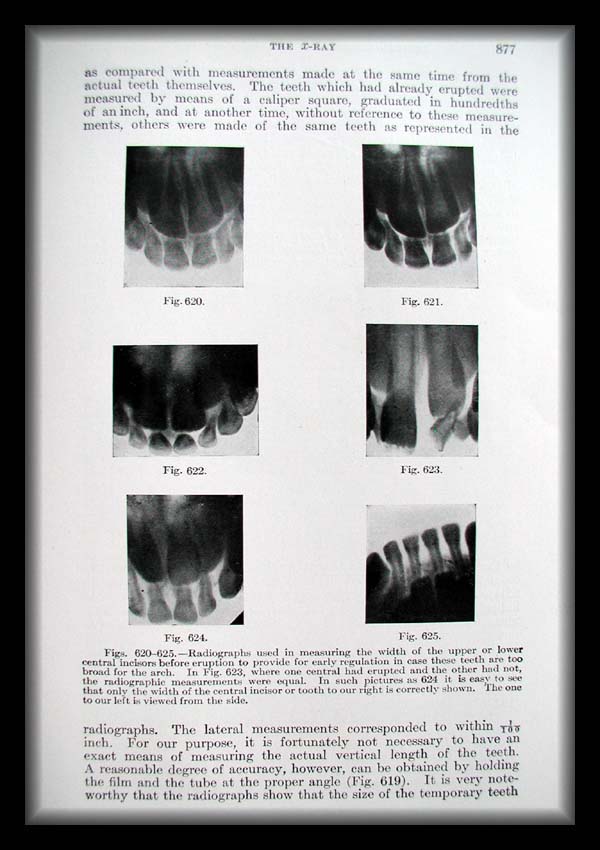

Page0877